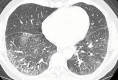

In the era of Precision Medicine, diagnostic imaging plays a key role in initial diagnosis and treatment response assessment in thoracic manifestation of various rheumatic disorders; resulting in increased dependency on imaging for treatment planning. Chest radiographs serve as a good initial screening tool for assessment of emergent and urgent thoracic conditions, e.g., pneumothorax, pulmonary edema, consolidation and pleural effusions. Cross-sectional imaging techniques, e.g., computed tomography (CT) and positron emission tomography-computed tomography (PET-CT) are most commonly utilized to evaluate more detailed pulmonary and mediastinal manifestations of rheumatic conditions. Magnetic resonance imaging (MRI) and ultrasound are most commonly used in cardiovascular, neural and musculoskeletal structures. This review article aims to highly key common thoracic imaging findings of rheumatic disorders, highlighting imaging test of choice for the particular disorder.